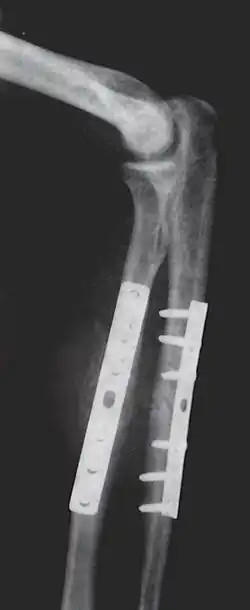

- Repair fracture of radius/ulna

- Repair fracture of the distal part of radius

- Repair of femoral shaft fracture